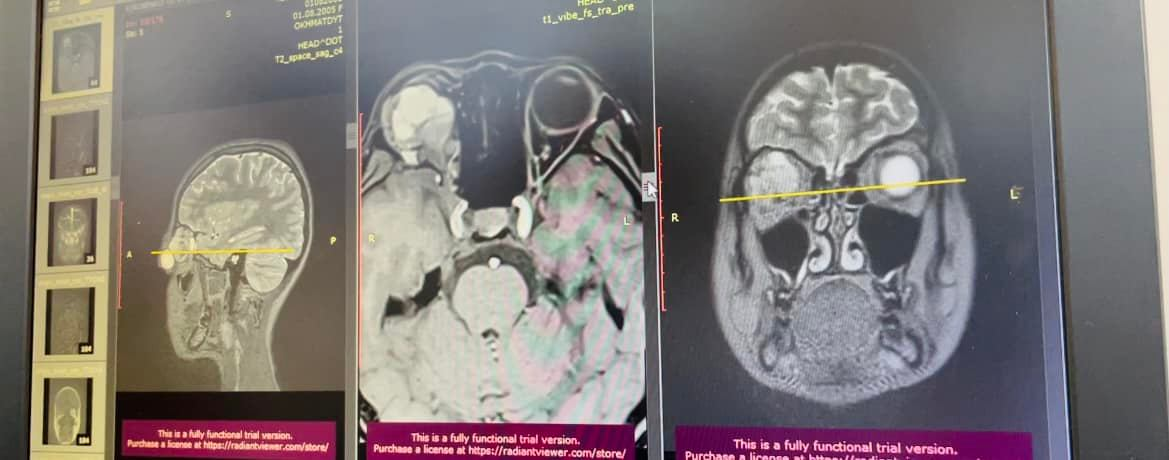

Наконец медикам удалось объяснить патологию - это огромная опухоль за глазом в орбите. Опухоль была словно "спаяна" со зрительным нервом и мышцей глаза, она выдавливала глазное яблоко Лизы.

Операция была непростой и длилась четыре часа: проводили ее ведущие специалисты клиники нейрохирург Павел Плавский и детский врач-офтальмолог Леся Лисица. Специалистам удалось удалить большую часть опухоли и сохранить функцию и мышцы глаза. Кроме того, был достигнут косметический эффект: медики считают, что глаз со временем примет нормальное положение и никто не подумает, что девочка десять лет страдала от страшной болезни.